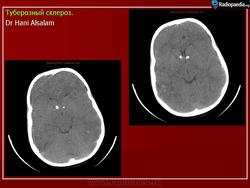

Туберозный склероз

Приложения:

1.tu_.slayd156.jpg2.tu_.slayd157.jpg3.tu_.slayd158.jpg4.tu_.slayd159.jpg5.tu_.slayd160.jpg